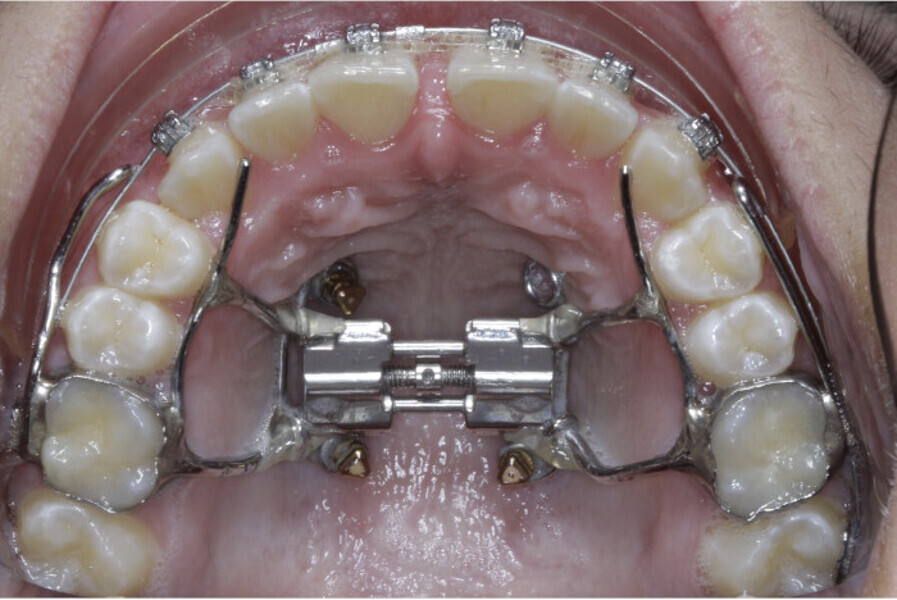

New Age orthodontics and orthopaedics with temporary anchorage devices